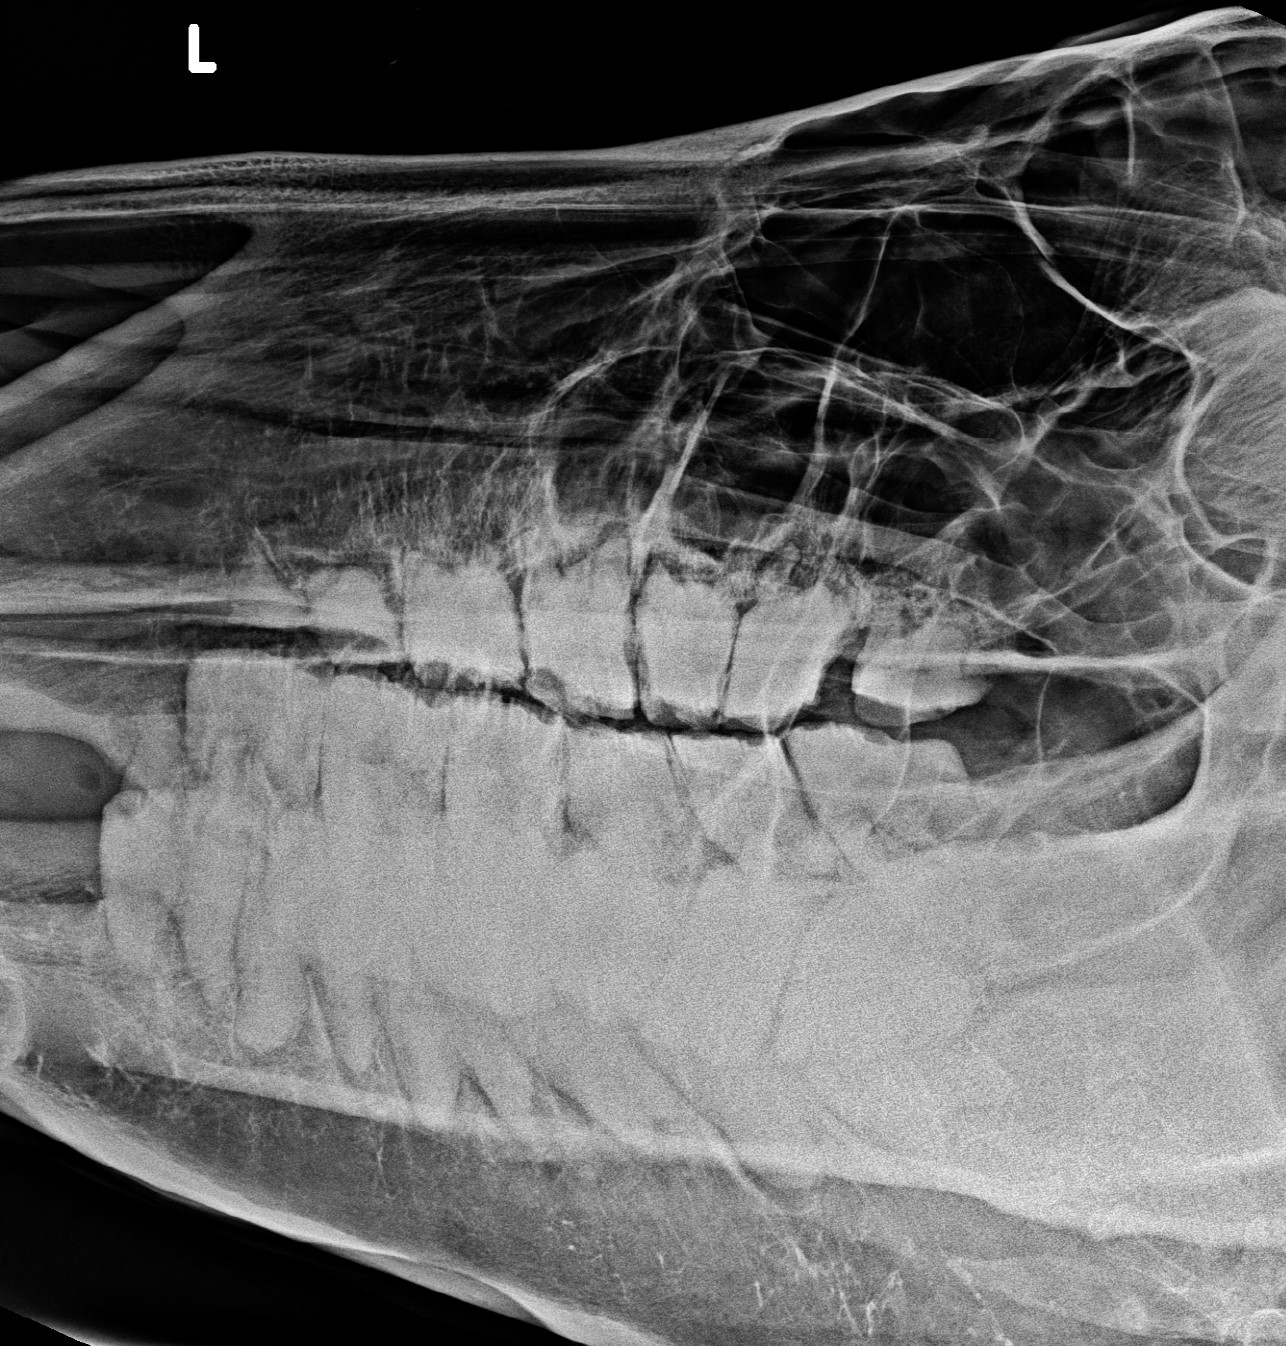

Rx 30 jährig

Backenzähne Oberkiefer 30-jährig